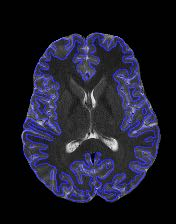

Fetal cortical plate segmentation is essential in quantitative analysis of fetal brain maturation and cortical folding. Manual segmentation of the cortical plate, or manual refinement of automatic segmentations is tedious and time-consuming. Automatic segmentation of the cortical plate, on the other hand, is challenged by the relatively low resolution of the reconstructed fetal brain MRI scans compared to the thin structure of the cortical plate, partial voluming, and the wide range of variations in the morphology of the cortical plate as the brain matures during gestation. To reduce the burden of manual refinement of segmentations, we have developed a new and powerful deep learning segmentation method. Our method exploits new deep attentive modules with mixed kernel convolutions within a fully convolutional neural network architecture that utilizes deep supervision and residual connections. We evaluated our method quantitatively based on several performance measures and expert evaluations. Results show that our method outperforms several state-of-the-art deep models for segmentation, as well as a state-of-the-art multi-atlas segmentation technique. We achieved average Dice similarity coefficient of 0.87, average Hausdorff distance of 0.96 mm, and average symmetric surface difference of 0.28 mm on reconstructed fetal brain MRI scans of fetuses scanned in the gestational age range of 16 to 39 weeks. With a computation time of less than 1 minute per fetal brain, our method can facilitate and accelerate large-scale studies on normal and altered fetal brain cortical maturation and folding.